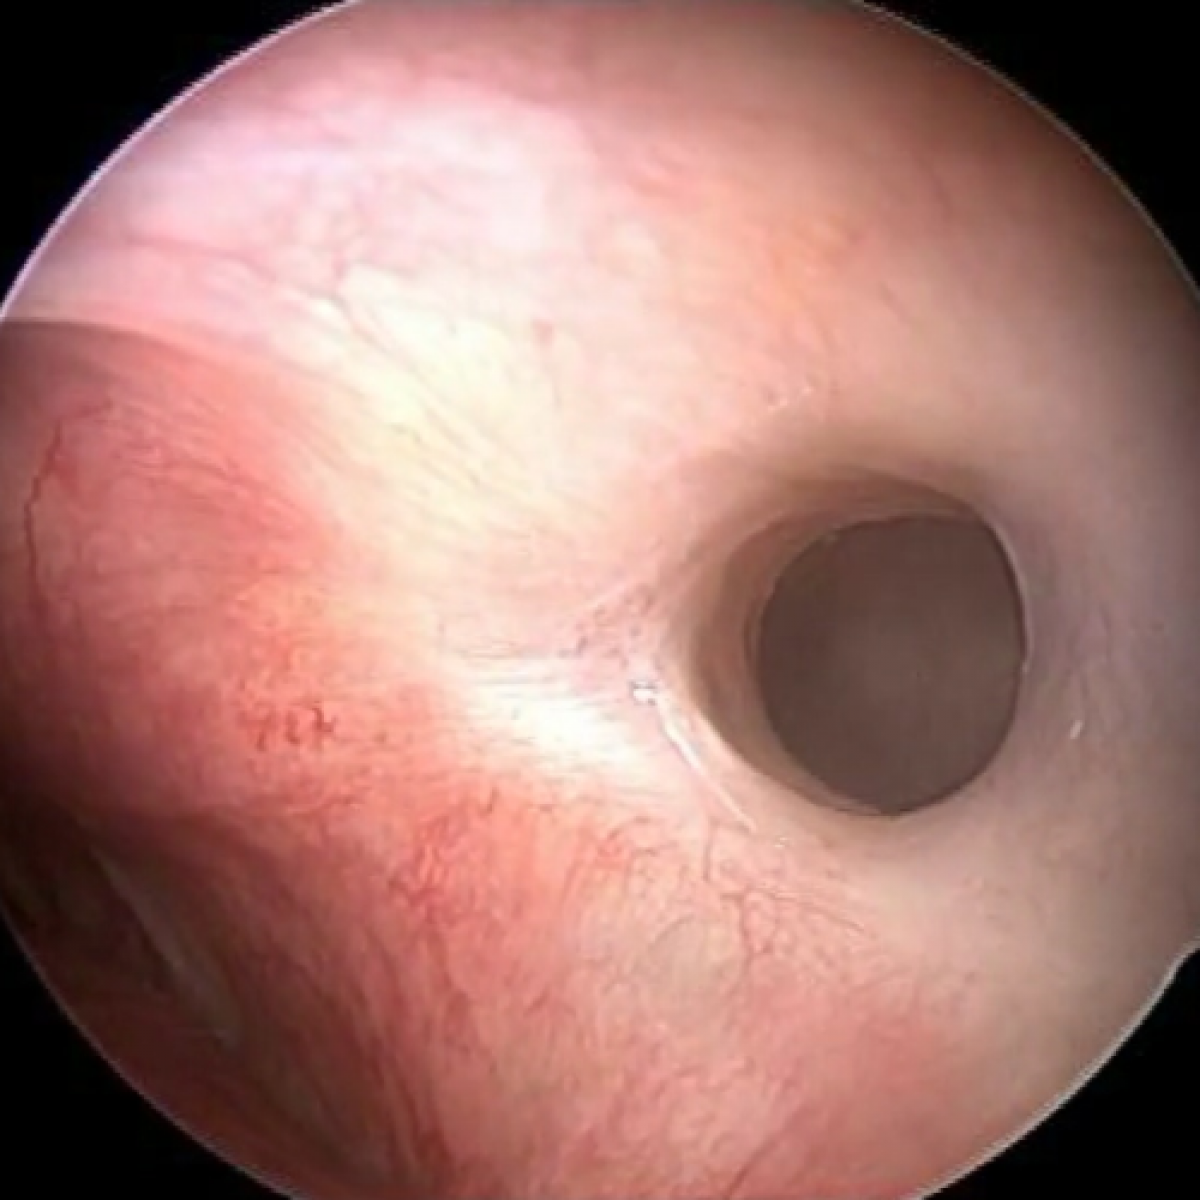

Complete left uncinectomy, medial antrostomy, dranage of the purulent secretions from the sinus, frontal sinusotomy and ethmoidectomy were performed. Granulation tissue was also removed from the maxillary sinus and sent for histological examination.